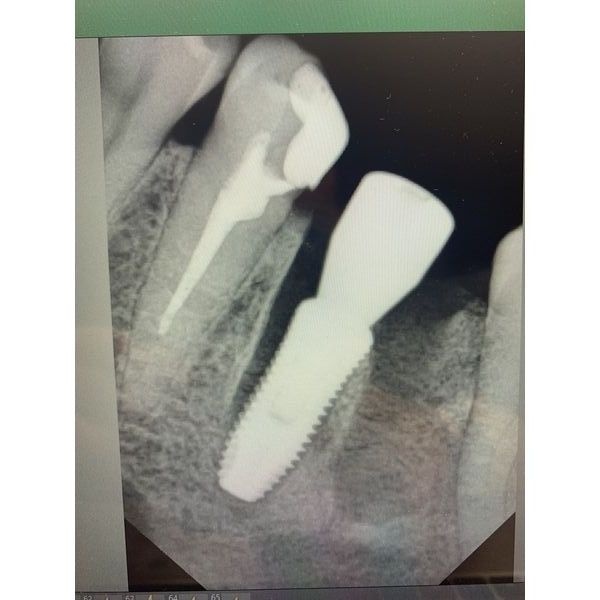

КЛКТ показала обширный очаг снижения плотности тканей вокруг верхушки корня зуба 4.6.

- установили имплант конической формы с торком (силой) 50 нсм: диаметр — 4,5, длина — 12 мм;